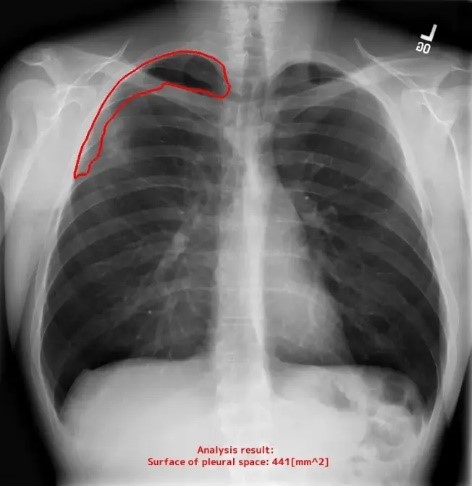

胸腔内空気含有面積を自動計測

X線画像から、空気が含まれる領域の面積を測定し、その領域を明示的に区別して表示します。